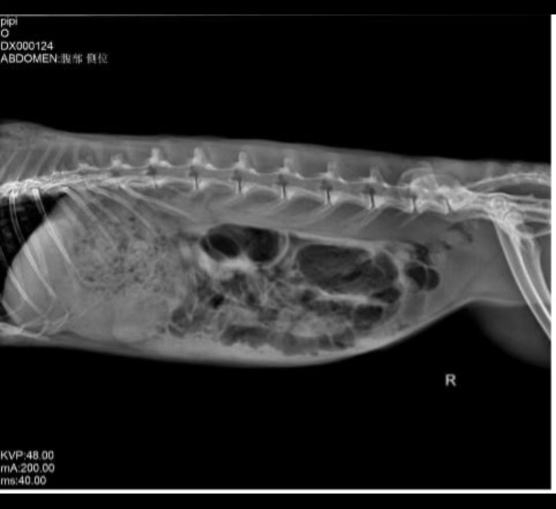

X-ray imaging revealed severe cecal bloating and food accumulation in the stomach. We advised the owner to be cautious when reviewing the images, as they could be unsettling.